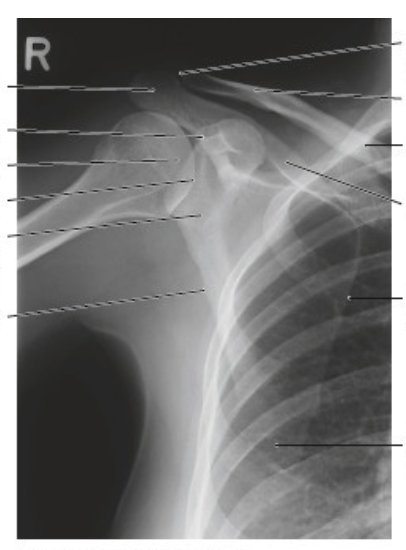

Landmarks of the scapula include the __, the __ process, __ and __ angles, the __ and __ and lateral borders

Landmarks of the scapula include the acromion, the coracoid process, superior and inferior angles, the spine and medial and lateral borders

Pectoral girdle: 2 bone components - clavicle and scapula

Clavicle articulates at the ___ joint

Clavicle articulates at the acromioclavicular joint